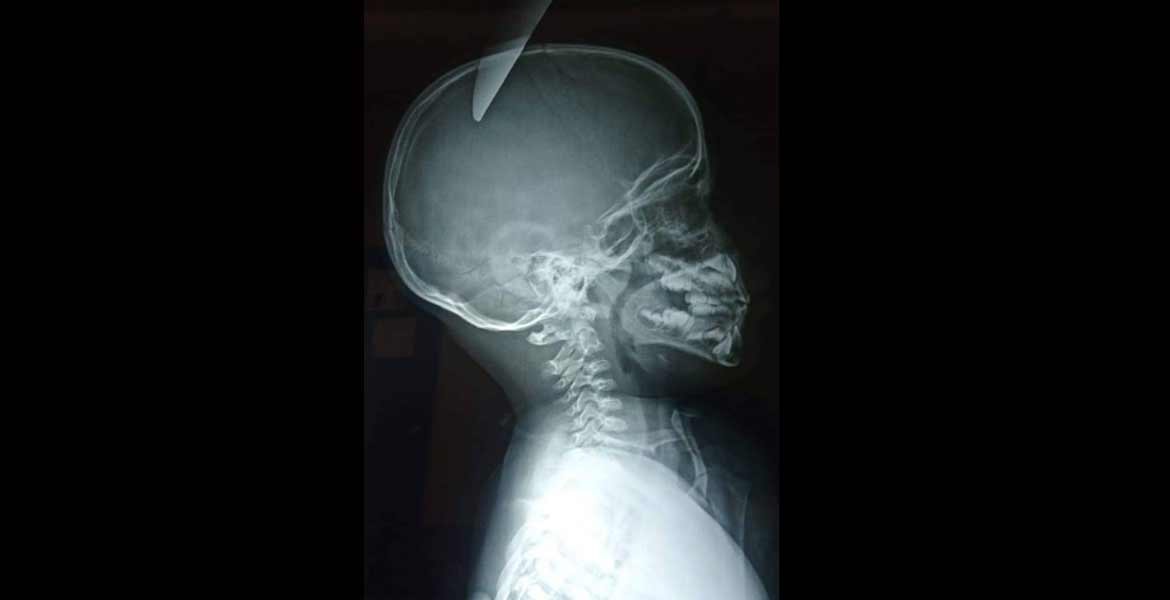

PUERTO PEÑASCO, Son.- El menor de 5 años de edad al que otro niño de 7 años de edad le clavó un cuchillo en la parte derecha de la cabeza en Puerto Peñasco, Sonora, fue trasladado a Mexicali y está siendo atendido en el Hospital General de Mexicali (HGM).

Cabe destacar que la parte derecha de la cabeza, por donde entro el objeto punzocortante, es la encargada de las funciones motoras.